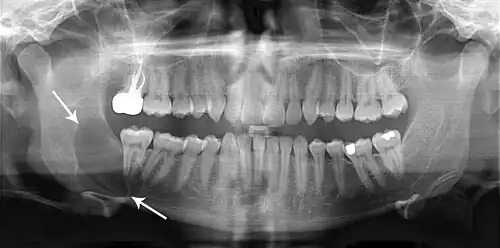

Aspectos radiográficos e histológicos

Radiograficamente, o QO se caracteriza como uma lesão radiolúcida uni ou multilocular, de bordas bem delimitadas e halo esclerótico, podendo ou não estar associada a um dente incluso.[4] Lesões maiores tendem a ter um aspecto multicístico festonado (aspecto de "bolha de sabão" ou de "favo de mel"), enquanto lesões menores tendem a ser unicísticas.[4] As lesões podem apresentar comportamento agressivo, com reabsorção óssea e dos dentes, deslocamento dos dentes e expansões ósseas.[5] Cerca de 25 a 40% dos queratocistos são associados a dentes inclusos.[4] Queratocistos menores podem ser confundidos com cisto dentígero, cisto radicular ou cisto periodontal lateral.[6]

Na tomografia computadorizada de feixe cônico (TCFC), o QO e o ameloblastoma possuem radiodensidades muito semelhantes, mas o ameloblastoma apresenta expansão da cortical óssea e poucas áreas de alta densidade tecidual.[7]